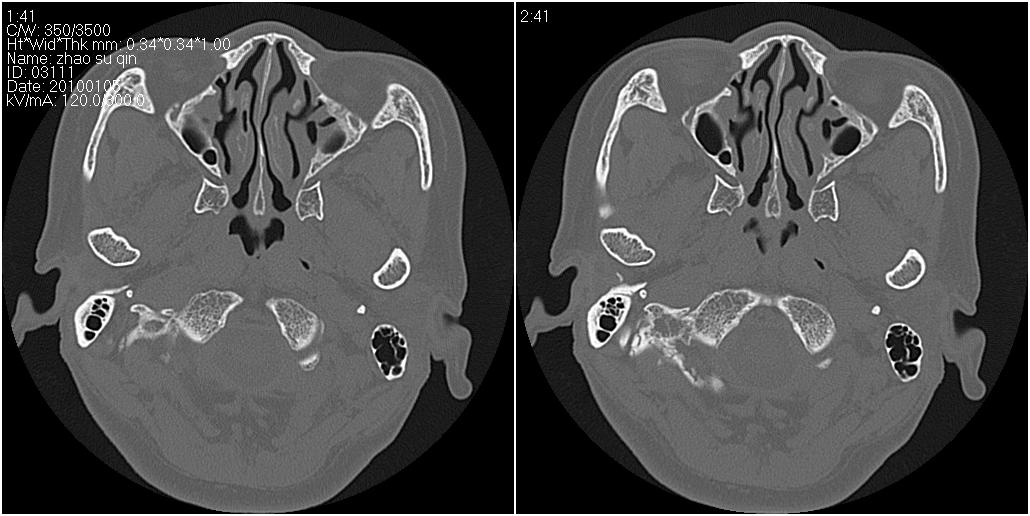

标题: CT24015:一个头部外伤患者进行鉴定,除了左侧筛板骨折,哪 [打印本页]

标题: CT24015:一个头部外伤患者进行鉴定,除了左侧筛板骨折,哪

看了几遍,其余未见明显骨折征。

左眶下裂部好像有骨折 似有小碎骨片

1)左侧筛板骨折。2)双侧筛窦炎症(或积血)。

其余未见明显骨折征。